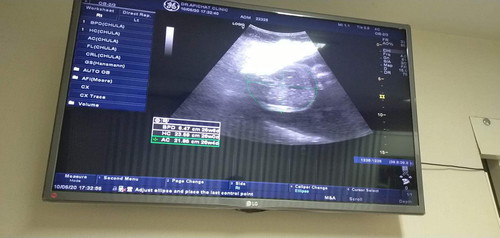

ขอดูภาพอัลตร้าซาวด์ แม่ๆหน่อยจ้า บ้านนี้27+1w

แม่ๆ27wได้ลูกหญิงลูกชายกันบ้างจ้า บ้านนี้ยังไม่แน่ใจจ้าน้องเอาเท้าปิดไว้แต่80%หมอบอกหญิงเพราะหากระเจี๊ยวน้องไม่เจอเลยหาทั่วแล้ว ?

ภาพนี้ซาวด์ตอน20Wค่า แฝดช-ชค่า